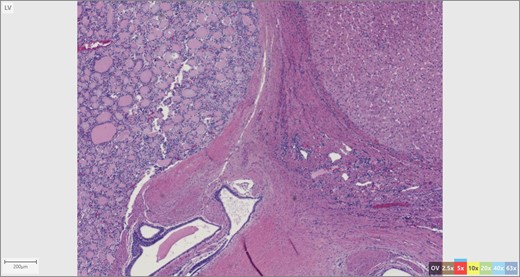

The patient’s surgical pathology was consistent with a low-grade neuroendocrine neoplasm arising within a mature cystic teratoma. The neoplasm took up 25% of the tumor volume and the rest was occupied by elements of a mature cystic teratoma. Histologically, squamous epithelium, sebaceous glands, thyroid, salivary gland, urothelium and gastrointestinal epithelium were all demonstrated (Figs 2–4). Final immunohistochemical analysis showed that the neuroendocrine neoplasm was reactive for: synaptophysin, AE1/AE3, STAT B2 and non-reactive for: CK 20, GATA3, CDX-2, CK 7, PAX 8, TTF 1, p 16, mammoglobolin, glypican 3, beta catenin, CD 117, DOG 1 and inhibin; thus, supporting its neuroendocrine origin from gastrointestinal tissue and consistent with a carcinoid tumor [12].

Skin adnexae and glandular elements of the mature cystic teratoma.